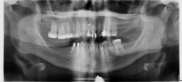

Dientes impactados

Los dientes impactados pueden provocar reabsorción radicular, requerir intervención quirúrgica para exponerlos y alinearlos en el arco, o extracción con una oclusión final comprometida.